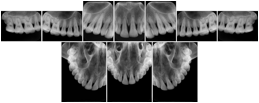

2. A patient requests cosmetic surgery to enhance their facial appearance. The case requires consultation between an orthodontist in New York and an oral surgeon in California. The cephalometric series of 2D projections constructed from the volumetric CT data that is used for the discussion is arranged by a Structured Display for transfer between the two practitioners.

Cephalometric Series Structured Display

Figure OO-2. Cephalometric Series Structured Display